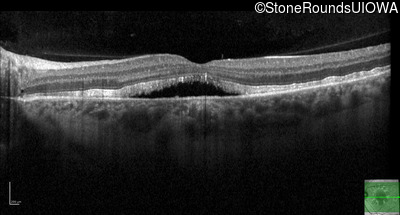

Best Disease (IIB)

Age at visit: 51 years

Age at visit: 52 years